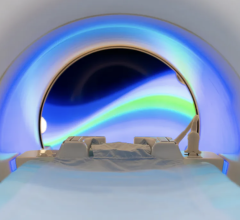

November 27, 2017 — At the 103rd Scientific Assembly and Annual Meeting of the Radiological Society of North America (RSNA), Siemens Healthineers debuted GOKnee3D, a magnetic resonance imaging (MRI) application that drastically shortens the time required to perform comprehensive diagnostic exams of the knee. Currently, a typical knee examination can be roughly 20 minutes. GOKnee3D enables a push-button, high-resolution diagnostic 3-D knee exam in just 10 minutes. The acquisition of high-resolution isotropic 3-D images subsequently allows flexible evaluation of the images in all possible planes, including double oblique and curved planar. Increasing MRI efficiency in this manner is especially important because knee examinations are the third most common type of MRI examination, accounting for 11 percent of all scans.

The volume acquisition of GOKnee3D is based on a CAIPIRINHA SPACE protocol, which enables higher scan speeds and optimal image reconstruction with better signal quality than in previous technologies. Supported by dedicated, high-channel knee coils as well as automated field-of-view adaptation based on machine learning and artificial intelligence, the MR scanner acquires the volume data of the knee joint at the touch of a button.

To develop and clinically validate the technique, Siemens Healthineers collaborated with Johns Hopkins University in Baltimore. “GOKnee3D enables comprehensive evaluation of internal derangement to the knee,” said Jan Fritz, M.D., assistant professor of radiology and radiological sciences at the Johns Hopkins University School of Medicine. “The fully automated CAIPIRINHA SPACE protocol provides high-quality MR imaging in 10 minutes and ensures consistency of image quality and operational efficiency. The high spatial resolution isotropic data sets help to visualize abnormalities with high accuracy, enable reformations of virtually any imaging plane, and create high-quality 3-D-rendered MR images.”

GOKnee3D is U.S. Food and Drug Administration (FDA) 510(k)-pending. It is available as an upgrade for the Magnetom Skyra 3T and Magnetom Aera 1.5T MR scanners, with eventual rollout planned for additional MR scanners.